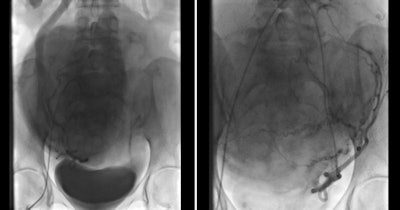

There has been increasing global interest in uterine artery embolization as the primary management tool for symptomatic uterine fibroids since the first report in 1995 by Ravina et al.6,7 The principle of UAE is to devascularize the uterine fibroids so as to induce irreversible ischemic injury that leads to necrosis and shrinkage of fibroids.8,9

This is achieved by selective catheterization of both uterine arteries under image guidance and injection of embolization particles.10 Polyvinyl alcohol (PVA) particles are commonly used, but the optimal type and size of the embolization particles is an ongoing debate.11 It is suggested to use particles larger than 300 µm to avoid untargeted ovarian embolization and uterine necrosis.12